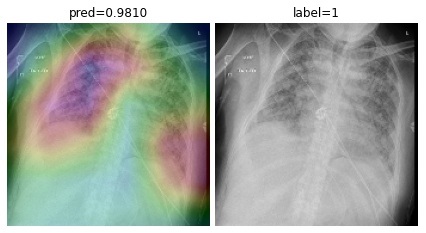

Appendix B More Grad-CAMs of the COVID-CXNet Model with Lung Segmentation Preprocessing

Refer to caption

Figure 21: Grad-CAMs from COVID-CXNet with lung segmentation module